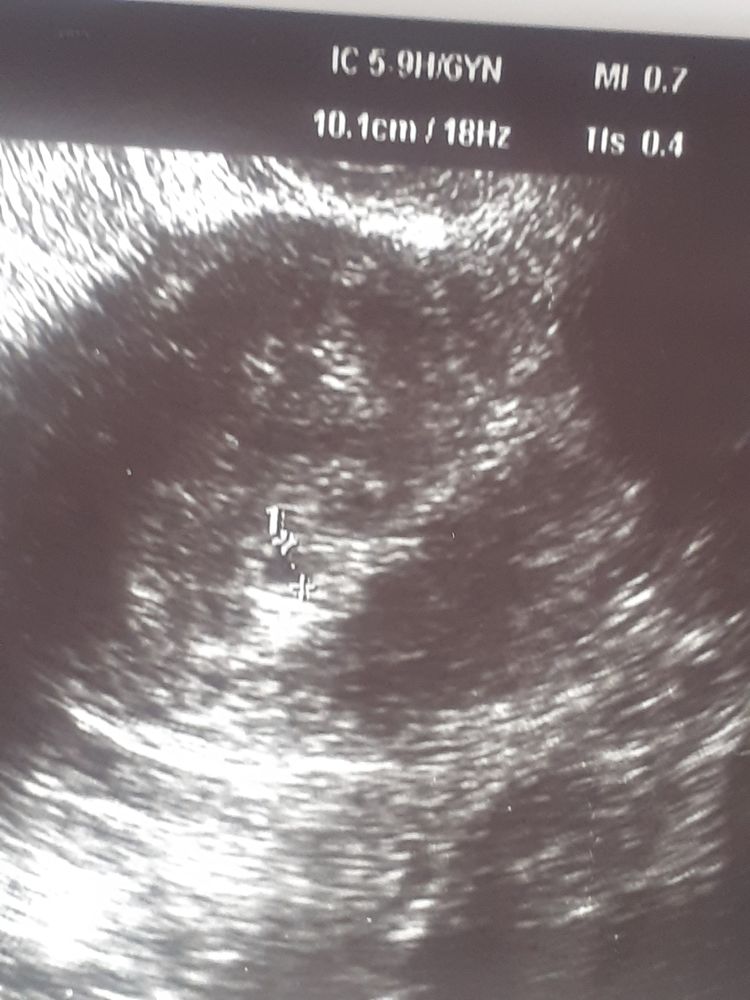

Читаю вашу историю и понимаю, что ситуация схожи)))) во-первых вы Алёна и я Алена)))) перенос у меня тоже был 2 августа, только одного эмбриона 4АА)))))) У МЕНЯ походу была поздняя имплантация, тк полосочка еле заметная на 7дпп, на 7дпп хгч -6 8дпп-19 10дпп-36 12дпп-165 14дпп-390 16дпп-779 18дпп-1278 20дпп-2065 Тоже переживала, что медленно растет, сегодня еще раз сдала хгч, результат завтра) На узи была на 18дпп, тк моя ре уходит в отпуск. По узи плодное яйцо и жм в матке)))) Я желаю вам удачи, верьте в своих крошек))) и пусть и у вас и у меня все получится)))